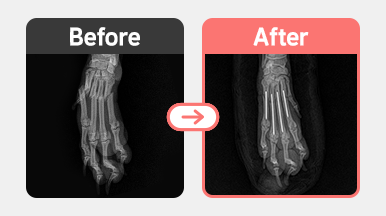

[요골 골절 수술] 말티푸 / 1살 / 우측 radius 횡골절 / plate 내고정술

2025-11-13